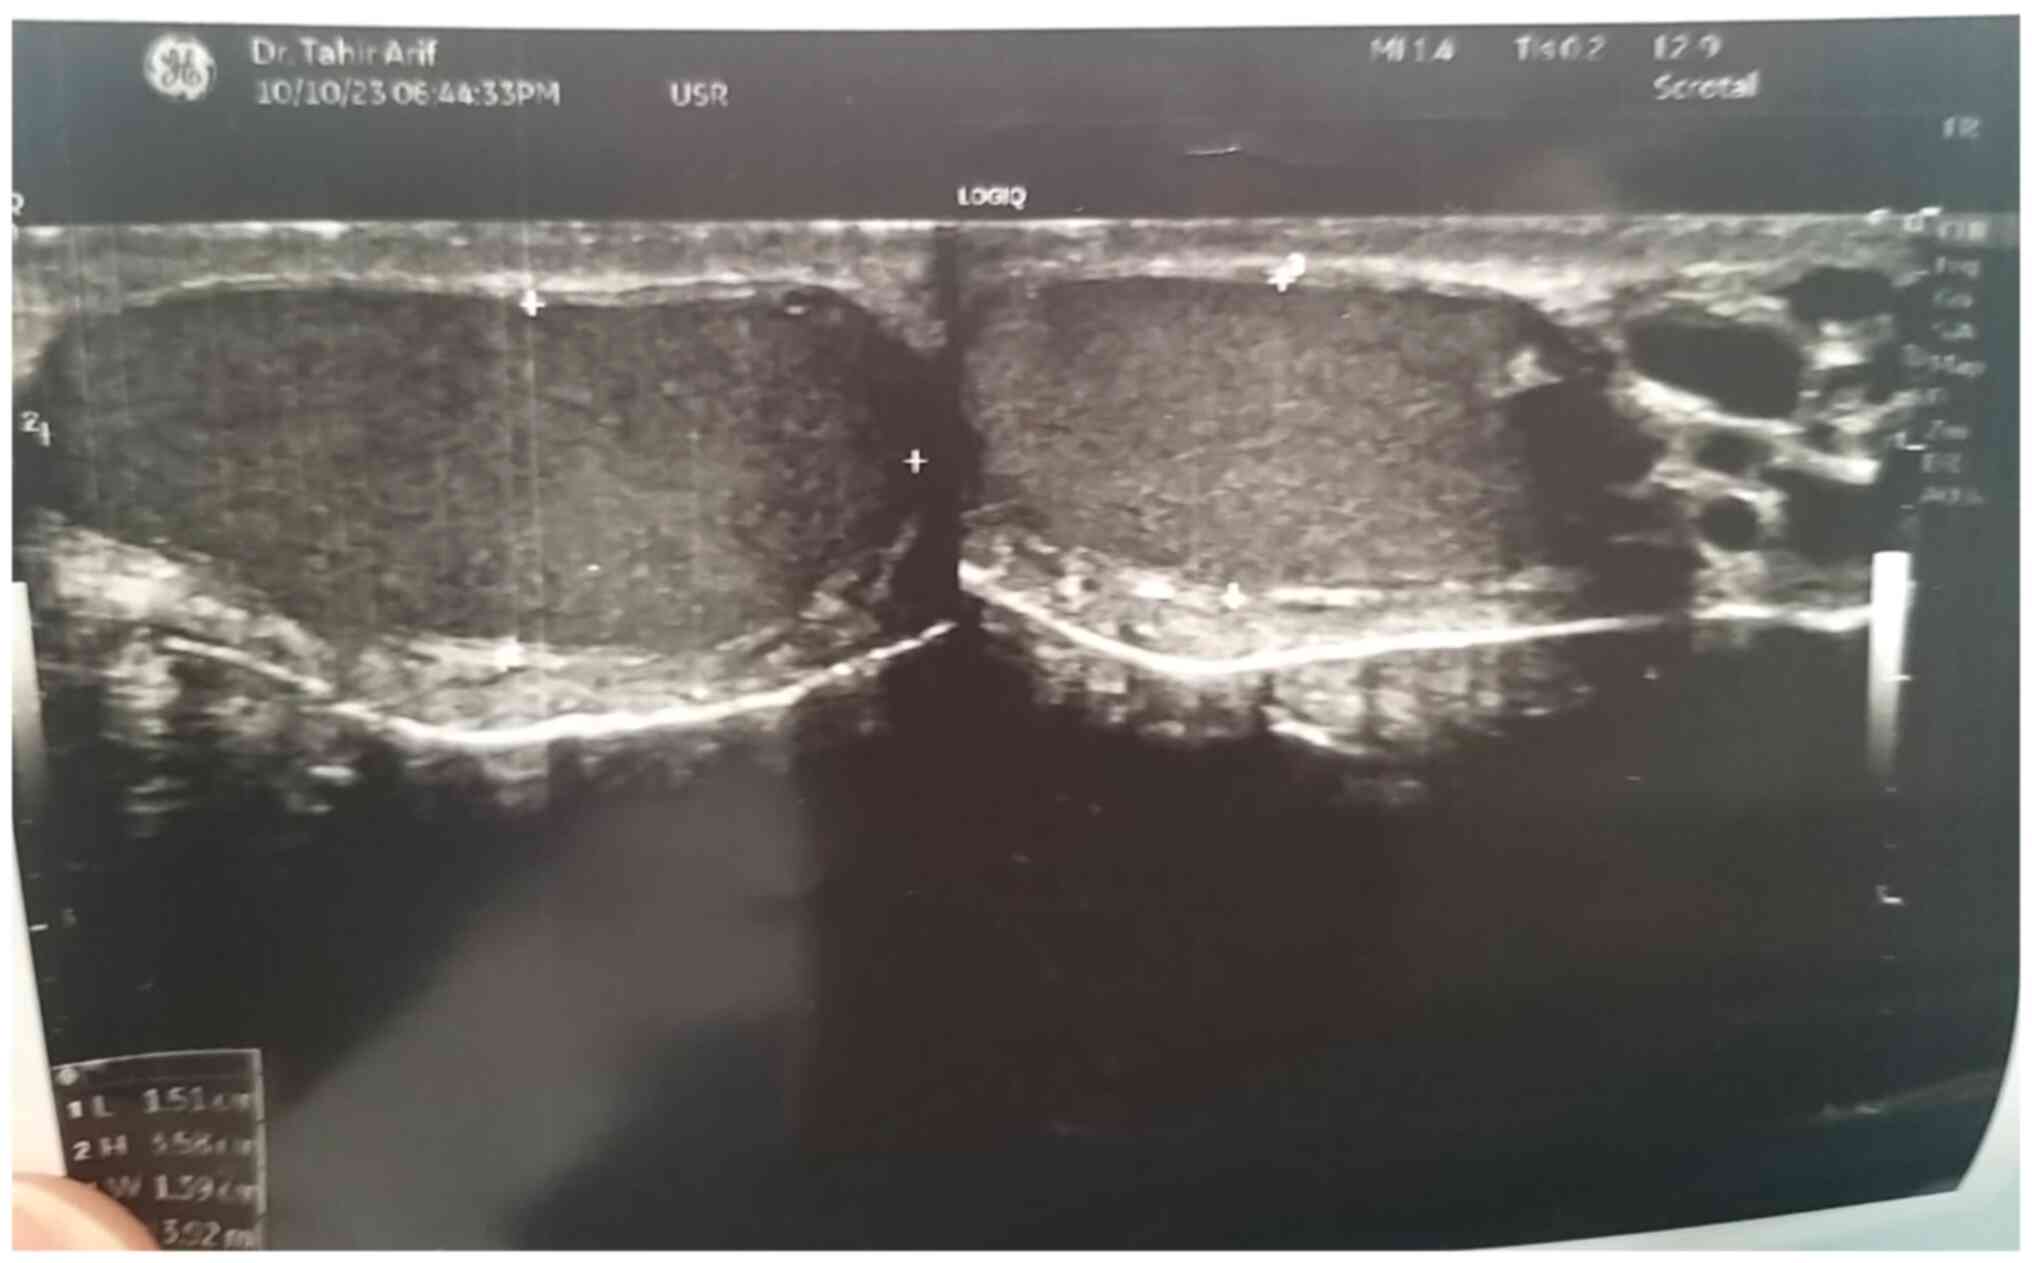

Semen uric acid crystals in azoospermia linked to Sertoli cell‑only syndrome: A rare case report

The occurrence of crystals in semen is rare, with spermine phosphate crystals being the only type commonly described. Uric acid crystal formation is significantly influenced by pH levels. The present study reported a rare case of uric acid crystals in the semen of a patient with azoospermia associated with Sertoli cell‑only syndrome (SCOS). A 28‑year‑old male with a four‑year history of primary infertility underwent clinical assessment, including a normal physical examination with small testes. Seminal fluid analysis revealed abnormal uric acid crystals. Elevated follicle‑stimulating hormone, luteinizing hormone and prolactin levels were observed. The diagnosis of SCOS was confirmed through testicular sperm aspiration. Azoospermia is a medical condition characterized by the absence of sperm in the semen, specifically the absence of sperm in the pellet obtained after centrifugation. It is classified into two primary types: Obstructive and non‑obstructive azoospermia. Non‑obstructive azoospermia is subdivided into three categories: SCOS, hypospermatogenesis and maturation arrest. The occurrence of SCOS in azoospermic males ranges from 26.3 to 57.8%. The diagnosis of azoospermia with SCOS can be achieved through the analysis of multiple semen samples, medical history, physical examination, hormonal analysis, histopathological examination and genetic testing. The presence of uric acid crystals in seminal fluid was first reported in patients with chronic prostatitis symptoms in 2005. Despite the rarity of crystals in semen, uric acid crystals were found in the semen of an azoospermic male with SCOS.

Figure 1

Figure 2